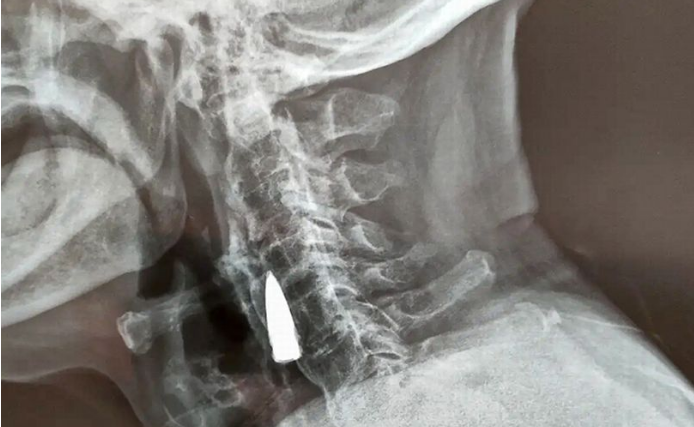

Ärzte entdeckten auf einem Röntgenbild ein Projektil, das bereits 77 Jahre im Nacken eines 95-Jährigen gesteckt haben muss, ohne, dass er sie bemerkt hatte.

Zhao He (95) ließ sich vor kurzem im Krankenhaus in Shandong, China, Röntgenbilder anfertigen. Dabei entdeckten die Ärzte eine Kugel im Nacken des Mannes. Bei dem Projektil handelt es sich um ein Überbleibsel aus dem Zweiten Weltkrieg. Die Kugel dürfte sich demnach schon 77 Jahre unbemerkt im Körper von Zhao He befinden.

Sein Schwiegersohn Wang zu dem Vorfall:  "Er wurde verletzt, als er während einer der Schlachten einen verwundeten Kameraden über einen Fluss trug." Wie durch ein Wunder hatte die Kugel He keine Probleme bereitet, obwohl sie schon so lange in seinem Hals steckt. Deshalb wird die Kugel auch nicht rausoperiert, da die Operation riskanter sei.